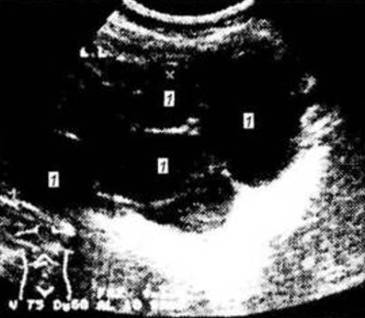

2. назовите метод и опишите рисунок

3. назовите метод и опишите рисунок